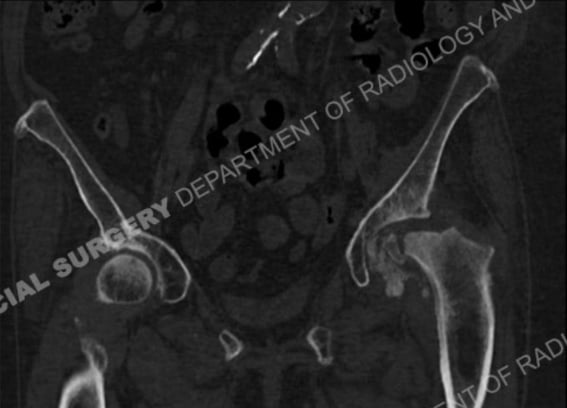

CT scans

CT examinations, also called CT scans (or “CAT scans”), are excellent for showing bones and osteophytes (bone spurs). CT examinations are also useful in providing guidance for therapeutic and diagnostic procedures.

CT scan of an arthritic hip showing bony femoral head debris